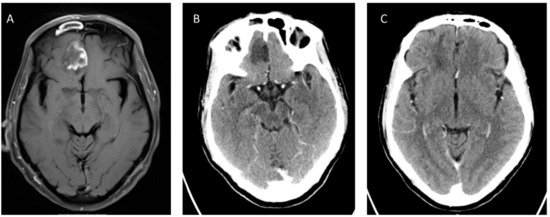

The three most frequent imaging findings in intracranial mucormycosis are cavernous sinus thrombosis, brain infarction and internal carotid artery occlusion [77,78]. Brain imaging shows signs of primarily parenchymal involvement, usually involving the inferior parts of the frontal lobes (Figure 1). Lesions may be either hypo- or hyperintense on T2-weighted series [73], and diffusion weighted imaging (DWI) series show markedly reduced diffusion [78]. An intriguing case report outlined the use of magnetic resonance spectroscopy to differentiate CNS mucormycosis from bacterial cerebritis [79]; additional validation of this modality is warranted. Metastatic cancer and the Tolosa–Hunt syndrome are the main differential considerations in patients with cavernous sinus syndrome [25].

Figure 1.

Cerebral mucormycosis. A 67-year old male with acute B-cell lymphoblastic leukemia, chemotherapy-induced neutropenia and high-dose corticosteroid treatment, developed sinopulmonary mucormycosis with cerebral extension involving the right frontal lobe (T1 weighted magnetic resonance (MR) image (A) and computed tomography (CT) (B)). Culture from sinus biopsy and stereotactic brain biopsy grew Rhizopus arrhizus. The patient was treated with Liposomal Amphotericin B (10 mg/kg per day) and Isavuconazole, without debridement of brain tissue. Follow-up CT after 4 months of treatment shows near-complete resolution (C). Courtesy: M. Weinberger and N. Carmi Oren.